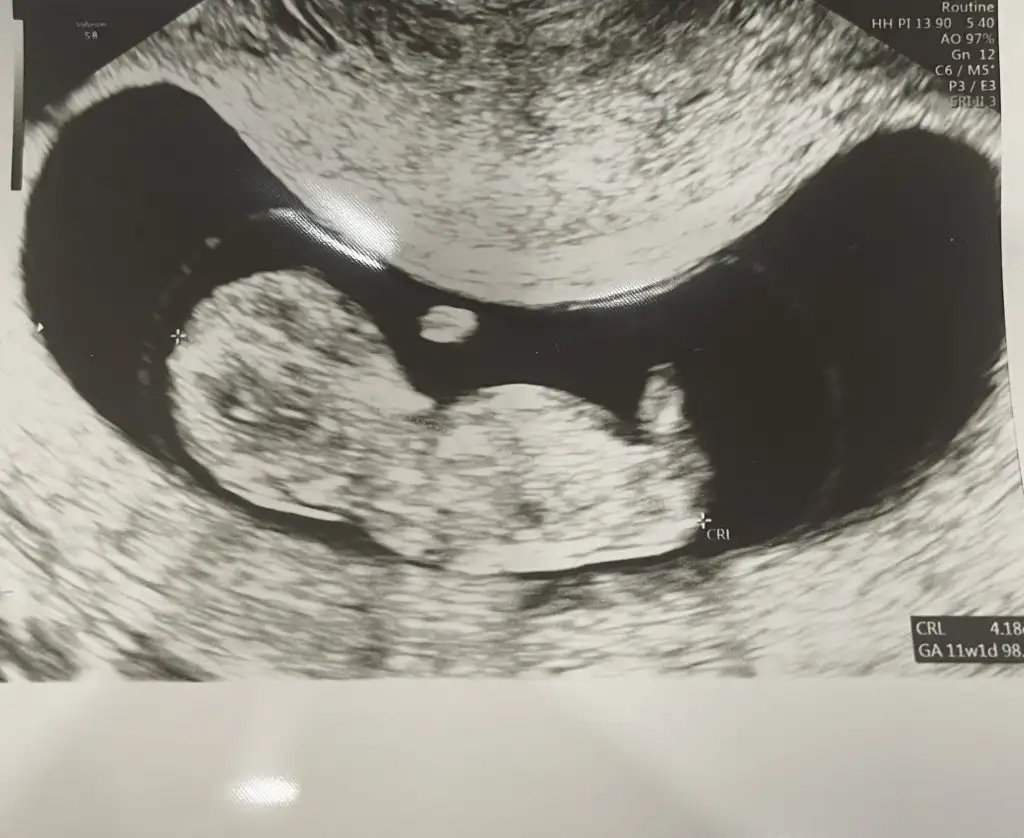

Bence erkek .Öyle hissettimHayırlı cumalar kızlar, bugün kendi Doktorumdan farklı bir doktora gittim.normal de çok ilgili bir dr,ama ameliyattan yeni çıkmıştı bir sürü hasta bekliyodu,bize de alelacele baktı. Dolayısıyla bebeğin cinsiyeti hakkında bir tahmin yürütmedi. Meraktan çatlicam sizce bu minnak neye benziyoEki Görüntüle 2941928

Canım merhaba benimkine de yorum yapar mısın sence cinsiyeti ne 2. çocuğum olacak ve çok merak ediyorumO kadarını bilmem de canım genel de söylediğim doğru çıkıyor az çok tecrübe edindim

Sizde erkek annesi olacaksınız sanırımCanım merhaba benimkine de yorum yapar mısın sence cinsiyeti ne 2. çocuğum olacak ve çok merak ediyorum

Kız galibaTeyzeleri bizimki daha küçük ama belki cinsiyet tahmini yaparsınız dedim

Daha net fotoğraf yok mu canım